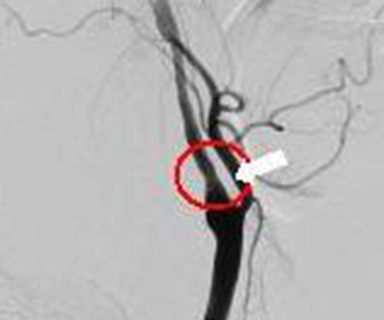

…その他にも、首の動脈が狭くなっていないかを調べたり、狭くなった血管を拡げる治療することができます。

内頚動脈狭窄

治療後(ステント挿入後)